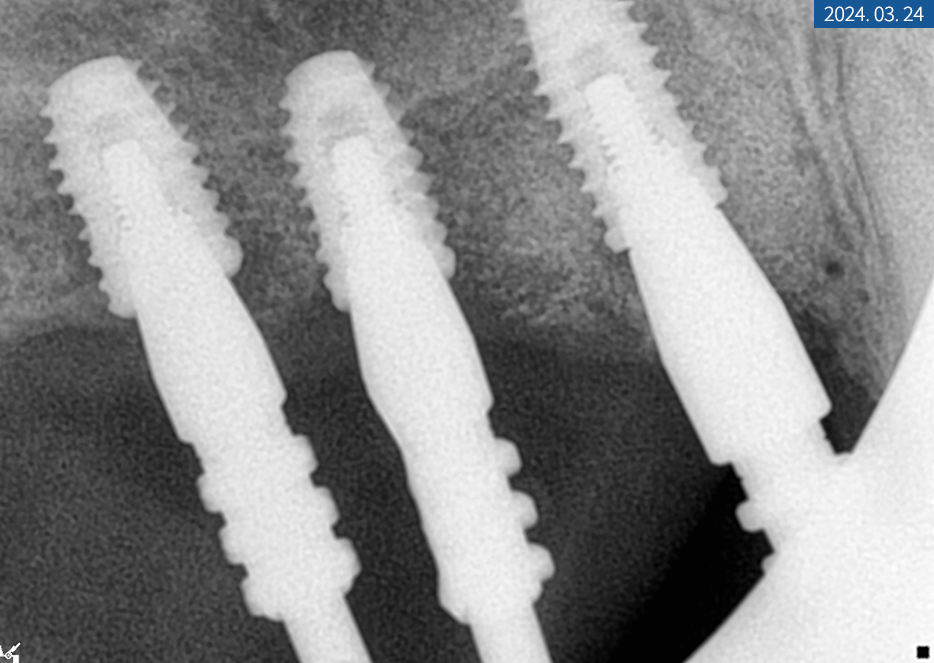

치근단 사진에서 좌측 상악

영구치(제 1대구치, 제 2대구치)가

손상된 곳은 신경 치료를 하기로 했습니다.

신경치료중인 환자분의 치근단 X-ray

3개월 후 좌측 픽스처 고정력을

ISQ 장비로 확인한 다음

힐링 지대주를 제거하고

코핑을 연결해서 인상과 교합 채득 후

임시 치아로 수복해 드렸습니다.